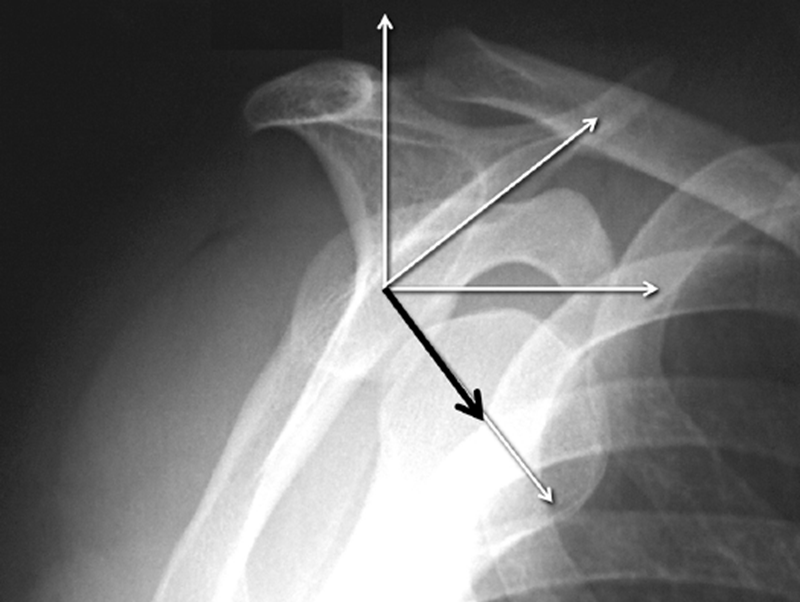

肩关节脱位是最常见的关节脱位,当第一次脱位时,医生给予手法复位,一段时间后往往再次出现,形成复发性脱位。频繁的脱位往往导致关节盂和肱骨头的撞击,骨与骨的撞击会带来两败俱伤的结果,肩胛盂的骨缺损,又称为骨性Bankart损伤。

肩关节脱位大都是前下脱位,但相对于肩胛盂来说是往前方脱位。

在4:30钟位逐步形成前下部骨缺损。